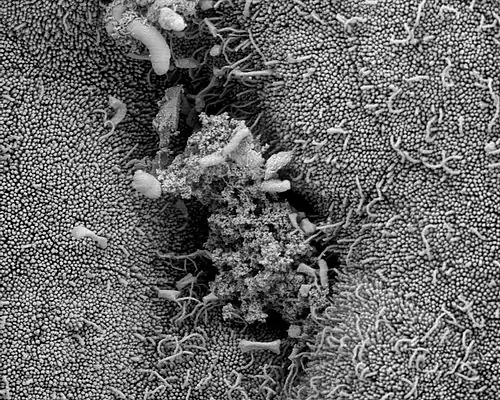

Das Endometrium (von altgriechisch ἔνδο(ν) éndo(n), deutsch ‚innen‘ und altgriechisch μήτρα mḗtrā, deutsch ‚Gebärmutter‘) oder deutsch die Gebärmutterschleimhaut ist eine dünne, rosafarbene Schleimhaut, welche die Innenwand der Gebärmutter (Uterus) bildet. Das Endometrium ist der Ort der Einnistung der befruchteten Eizelle (Nidation oder Implantation). Sollte sich keine Eizelle einnisten, folgt bei Primaten die Menstruation, bei welcher unter anderem die obere Schicht des Endometriums abgestoßen und ausgeschieden wird. Die Gebärmutterschleimhaut besteht aus einem Epithel, aus Drüsen (Uterindrüsen, Glandulae uterinae) und einem mit zahlreichen Blutgefäßen bestückten, stützenden Gewebe (Stroma) zwischen den Drüsen.

Bei Frauen im fruchtbaren Alter erfährt das Endometrium morphologische und funktionelle Veränderungen, die durch die Ausschüttung von Sexualhormonen gesteuert werden. So wird die Schleimhaut auf die Implantation vorbereitet. Vor der Pubertät oder nach der Menopause fehlt die zyklische hormonelle Beeinflussung, und das Gewebe erfährt keine Veränderungen. Mit der Menarche bereitet sich die Gebärmutter bei jedem Zyklus auf die Aufnahme einer befruchteten Eizelle vor. Dies geschieht durch das Wachstum und die Spezialisierung (Differenzierung) des Endometriums während eines Menstruationszyklus. Bei Primaten setzt sich das Endometrium dabei aus einer oberen (Funktionalis) und einer unteren Zellschicht (Basalis) zusammen.

Das Epithel der sogenannten Funktionalis nimmt vor der Menstruation an Höhe zu, die Drüsen produzieren verstärkt Sekret, die Durchblutung steigt und es treten sogenannte Pseudo- oder Prädeziduazellen auf. Bleibt eine Implantation aus, wird die Funktionalis des Endometriums bei Primaten abgesondert und ausgeschieden: Es kommt zur Regelblutung (Menstruation). Maßgeblich für den Untergang der Zellschicht ist der Entzug von Progesteron, das im Falle einer Implantation (auch Nidation oder Einnistung genannt) anhaltend vom Gelbkörper gebildet wird, der seinerseits durch das Signalhormon humanes Choriongonadotropin (HCG) aus dem Embryo stimuliert wird. Daher wird die Funktionalis in Vorbereitung auf die Menstruation auch Dezidua (lat. decidere ‚abfallen‘), genauer Dezidua menstrualis genannt.